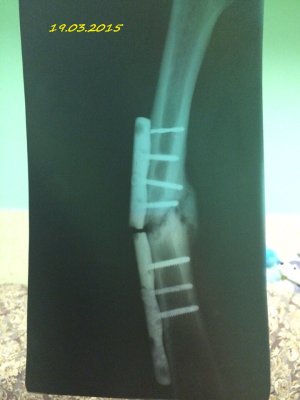

Здравствуйте! Мне 19 лет. 16.07.2014 года у меня случился закрытый перелом с/3 правого бедра со смещением. Произошло это так: я решила заниматься бегом. Каждый день бегала по стадиону минут 30-40. Получилось так, что я бежала, потом споткнувшись правой ногой, вернее как только я споткнулась, услышала хруст и упала на левую сторону. Сначала вообще не поняла, что произошло. Попыталась пошевелить ступней, особых болевых ощущений не испытала и решила попробовать встать, как только я попыталась поднять ногу, я увидела как у меня в бедре "шевелятся" кости. В итоге вызвали скорую, сделали рентген (все снимки я загрузила), поставили спицу под б/берцовую кость, почти под коленом, и я лежала 6 дней на вытяжке. 22.07.2014 года был проведен Экстрамедуллярный остеосинтез правого бедра пластиной АО (все пишу из выписки медицинской карты)Причем, прошу заметить на снимках может быть не видно, во время операции обломалось сверло, и пластину не закрепили по краям, я, конечно, мало что понимаю. 4.08.2014 года мне наложили гипс и отправили домой. 15.09.2014 года сняли гипс, я стала постепенно разрабатывать ногу, ходить, примерно 1.10.2014 года я стала ходить с тростью, все вроде бы шло на поправку. 23.10.2014 года меня выписали, и я уехала учиться в ВУЗ. Примерно вначале декабря я упала с лестницы(примерно со 2-ой ступеньки, при этом все это время я ходила с тростью). Стала болеть нога, я пошла в больницу, вновь снимок. Сказали все нормально-срастается. Назначили магнит(10 дней), отходила я на магнит. Все стало нормально, после НГ я могла ходить без трости, немного хромала, носила ее с собой, и когда уставала-ходила с ней. Вначале марта, примерно с 5-ого числа, стали мучить очень сильные боли, причем болело колено, очень тянуло берцовые кости, иногда беспокоило место перелома, вновь иду в больницу, опять снимок. И УЖАС! На снимке видно, как у меня кривится кость, чуть ли не ломаясь пополам, и переломана пластина. Мне говорят, что нужно делать операцию, врач сказал, что пластину не будут ставить повторно, эту уберут, все почистят и поставят штифт.